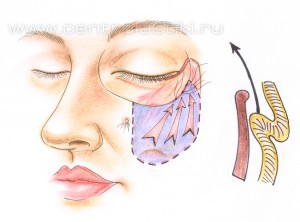

Рис. 9 Через боковую часть разреза выполняется отделение надкостницы от костей в проекции средней зоны лица вниз до крыла носа, обычно для этого используются эндоскопические инструменты. Рис. 11 Мобилизованные ткани прошиваются в верхненаружном углу и фиксируются к надкостнице выше наружного угла глаза. Рис. 12 Выполняется миопексия (фиксация мышцы окружающей глаз) Рис. 13 и кантопексия (фиксация наружного угла глаза), Рис. 14 затем удаляется избыток кожи Рис. 15. Этим достигается правильное положение глазной щели и удается добиться разглаживания мелких морщин. В конце операции кожная рана зашивается косметичным внутрикожным швом.

Рис. 11

Рис. 12